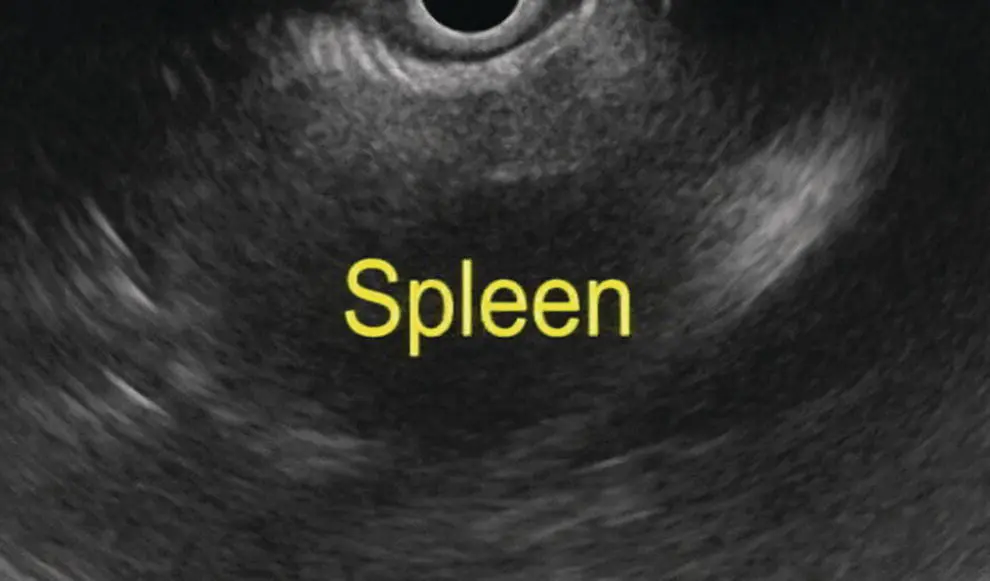

Spleen

The spleen appears as a homogeneous structure seen between the tail of the pancreas, left kidney, and gastric wall. With a radial scope it is imaged from the gastric cardia. It is similar to liver in echogenicity except that it is devoid of any ducts and vessels ( Figure 7.4). It can be easier to follow the splenic vein after visualizing the pancreas from the gastroesophageal (GE) junction. The splenic artery, splenic vein, renal vein, and the left adrenal are usually visualized as well while attempting to scan the spleen. The splenic vein can be easily traced along the inferior aspect of the body and tail of the pancreas; however, the splenic artery is tortuous and it is difficult to follow its course to the celiac trunk. With a linear scope one has to scan inferior to the left kidney and laterally to visualize the spleen ( Figure 7.5).

Figure 7.5 Image of spleen by linear ultrasound.